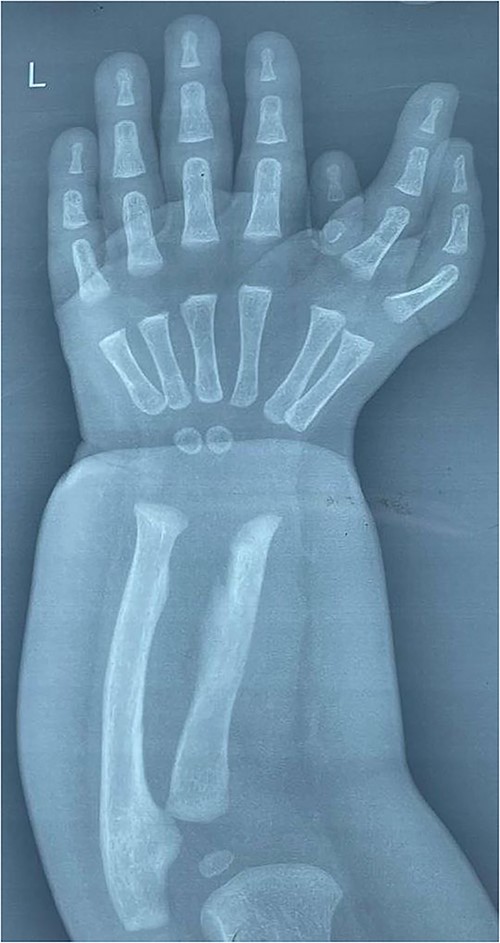

An 8-months-old girl: full-term, normal vaginal delivery, with normal perinatal medical history and no family history of congenital musculoskeletal anomalies presented with this congenital hand deformity since birth (Fig. 1).

Photographs preoperatively, showing the asymmetrical mirror hand with seven digits arranged in two groups.